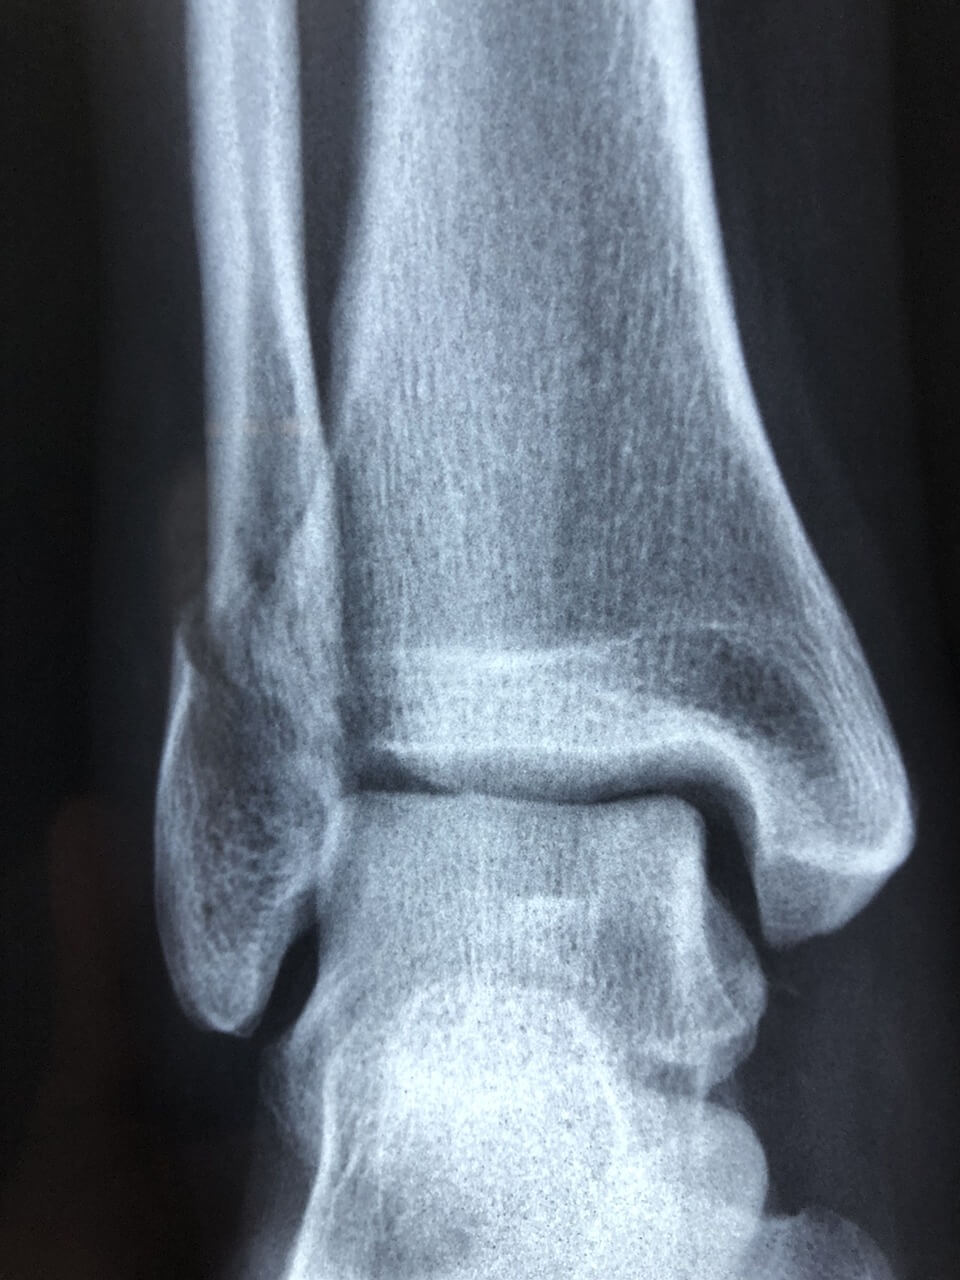

- 가벼운 충격에도 손목·발목 통증이 오래 감

- 검사 개요

- 이중에너지 X선 흡수계측(DEXA): 골밀도 표준

- 혈액검사: 비타민D(25(OH)D), 칼슘, 마그네슘

- 필요 시 척추 단순 촬영(압박골절 확인)